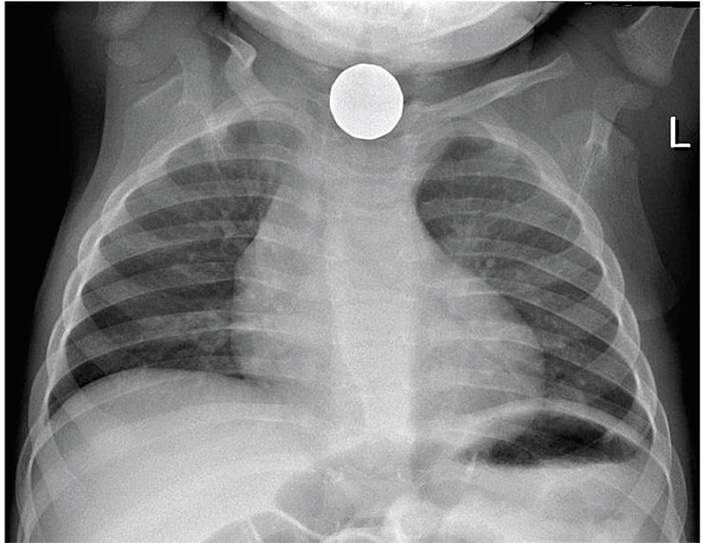

На рентгенограмме грудной клетки 9-летней девочки из Венесуэлы видна местная 25-центовая монета, застрявшая в верхней части пищевода. © CC BY-SA 4.0/ Isidro Ruiz, MD

Чего только не попадает в пищеварительный тракт, помимо пищи! Чемпионы здесь — дети, которые могут проглотить все, что угодно: от иголок и монет до больших шурупов; за ними идут люди с психиатрическими отклонениями и перевозчики наркотиков.

Около 90 % инородных тел, попадающих в желудок, выходит спонтанно через желудочно-кишечный тракт, но некоторые могут застрять в желудке или кишечнике, что иногда ведет к их непроходимости или перфорации. Предметы более 6 см в длину или более 2,5 см в диаметре редко проходят дальше желудка, но в аппендиксе находили даже батарейки! В 10 % подобных случаев требуются неоперативные вмешательства, а в менее 1 % — хирургическое лечение.